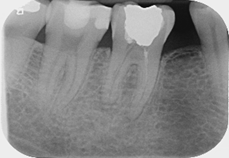

Fractured file removal and re-rct

Pre-op

Retrieved file

12 month review